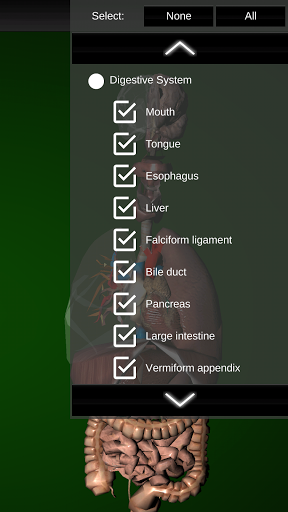

* Digestive system, including the stomach, small intestine, large intestine, and an animation of this system.

* Hide or show information.

* Added option to hide organs.

* Added the option to show the body contour.* Added 6 buttons that group different systems (digestive, reproductive, respiratory, etc).* Internal optimizations to improve performance.* Corrected the problem with the organ "Spleen".